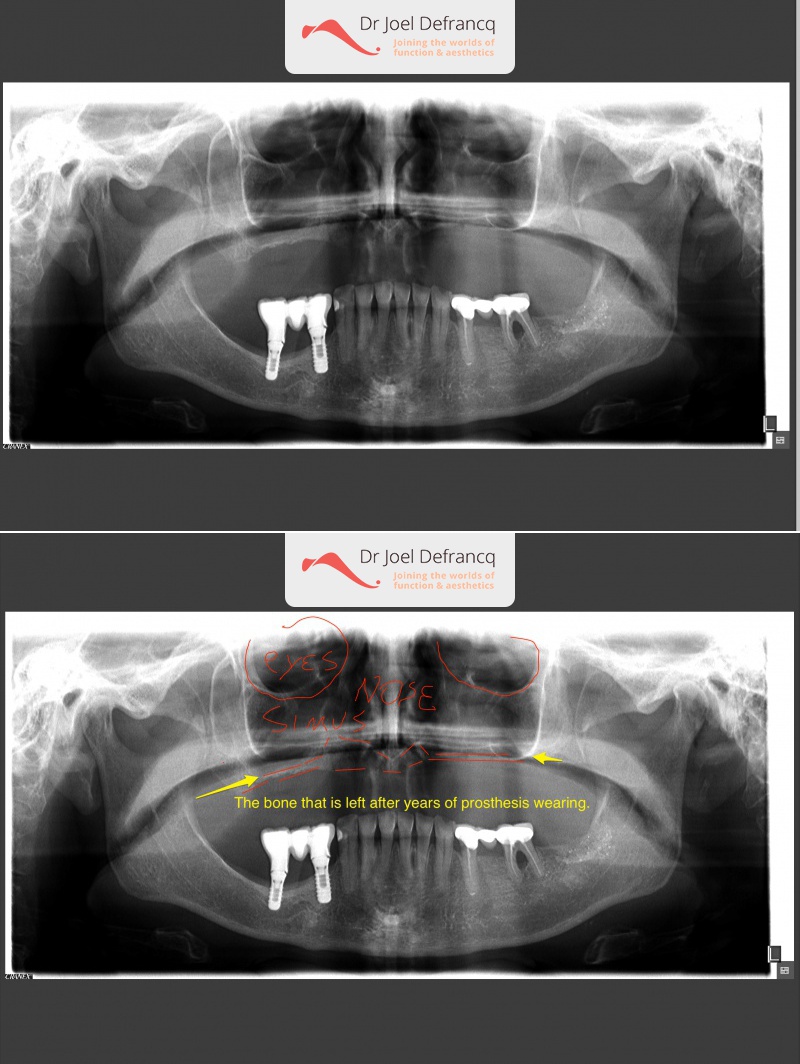

Bessina: "all on four " dentale implantaten

Behandeling tandheelkundige implantaten

- Vaste tanden op implantaten (bovenkaak)

- Vaste tanden op implantaten (onderkaak)

- Zygoma implantaten